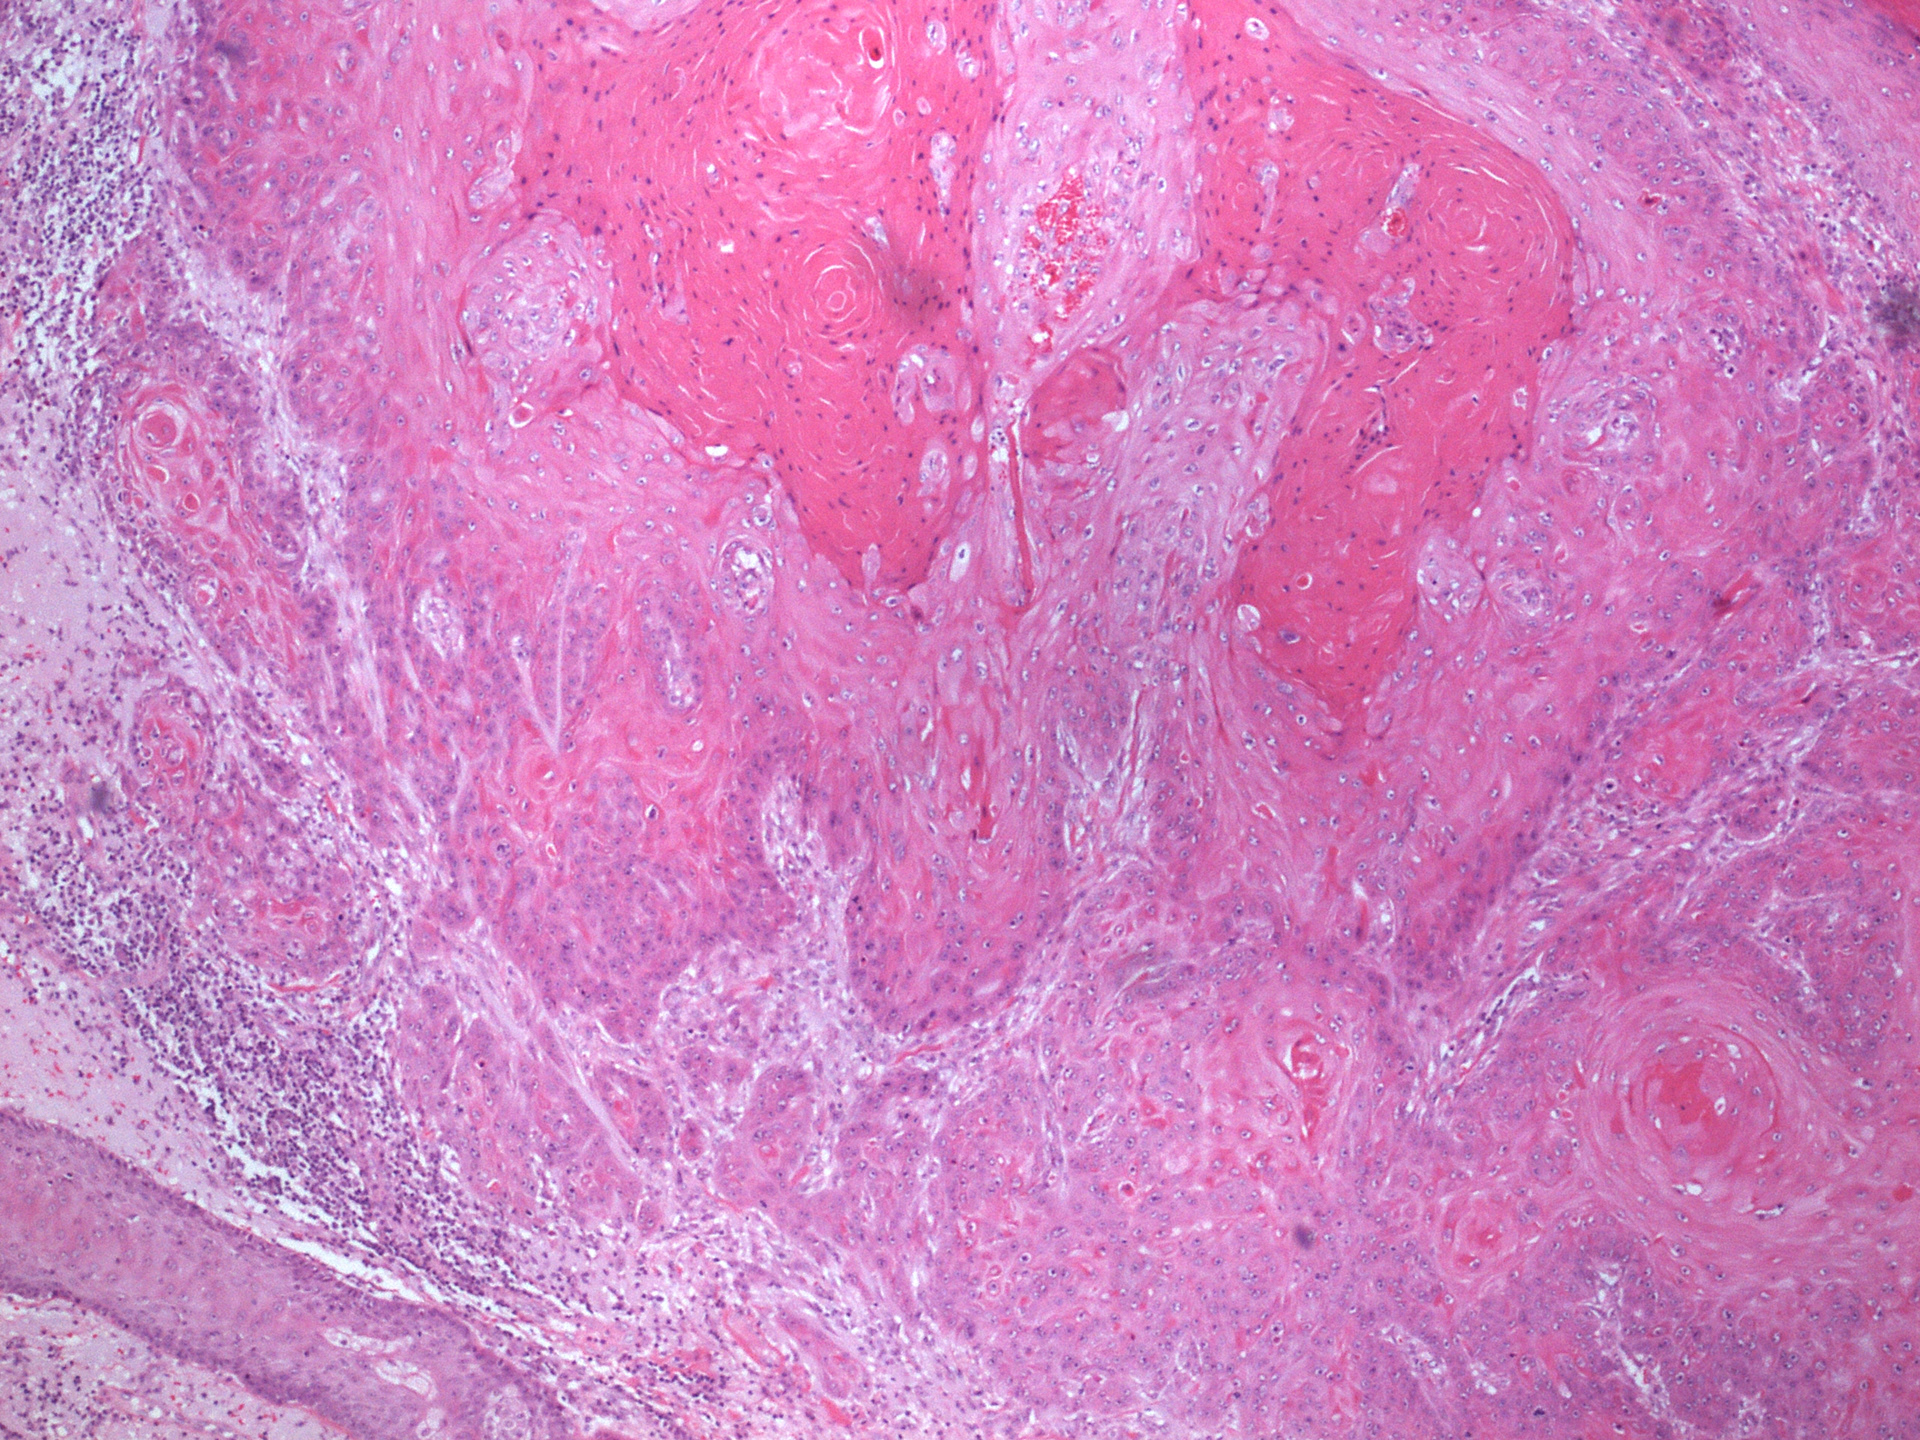

SQUAMOUS CELL CARCINOMA

One of the two images below is a low magnification view of skin. On the right of the image large hair follicles and their associated sebaceous glands can be seen. The sebaceous glands are made of large clear cells. On the left of this image you can see an infiltrating squamous cell carcinoma. Note the marked difference in colour and tone in contrast with the basal cell carcinoma. The higher magnification image shows keratin production by the tumour - proving this is a squamous cell carcinoma. The keratin is identified as much denser and deeply pink material towards the top right of the image.